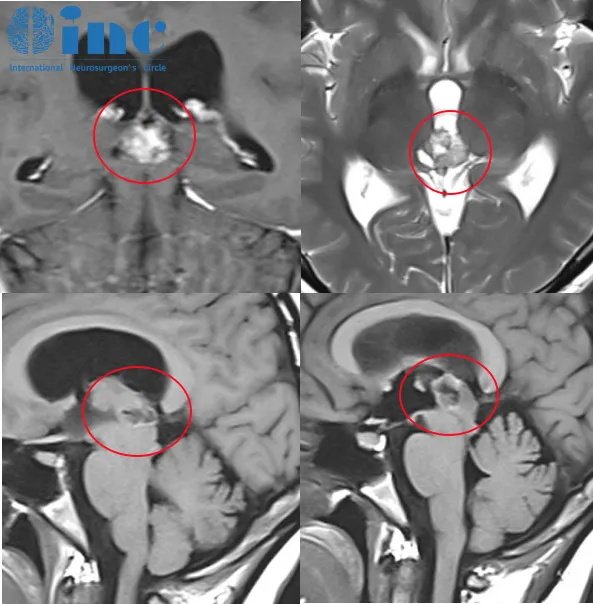

2021年11月,CT检查显示松果体占位性病变,大小为16*15*12mm,无特别神经功能障碍,随后进行颅脑核磁MRI,医生建议先观察3个月。观察结束后进行复查,建议手术治疗并告知相关风险。考虑到手术风险,晴晴选择继续保守治疗。

2022年9月再次复查,肿瘤伴幕上脑积水。除了偶有眩晕、脑涨,其他症状并不明显,晴晴还是选择了保守。

2023年3月再次复查时,肿瘤竟然长大了18*18*15mm,并出现幕上脑积水。临床症状不变化,医生建议再持续观察3-6月,但最终需要手术治疗。